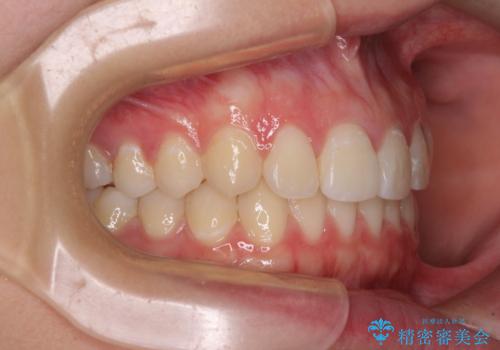

前歯のデコボコを改善 インビザライン矯正

- 口元のデコボコを気にして来院された患者様です。

前歯の捻れにより口元が閉じにくくなっていたため、歯列全体の側方への拡大と、歯と歯の間を少し削ってスペースを獲得することとしました。

ゴムかけをしっかりと行ってもらい、スッキリとした口元に仕上げることができました。